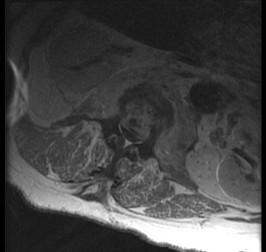

问题 男,67岁,背痛,发热,寒战半月余,有镰状细胞贫血病,请结合影像学检查,选择最可能的诊断 ( )

选项 A、脊髓空洞症 B、脊柱骨髓炎 C、椎体压缩骨折 D、脊柱转移瘤 E、脊柱结核

答案 B